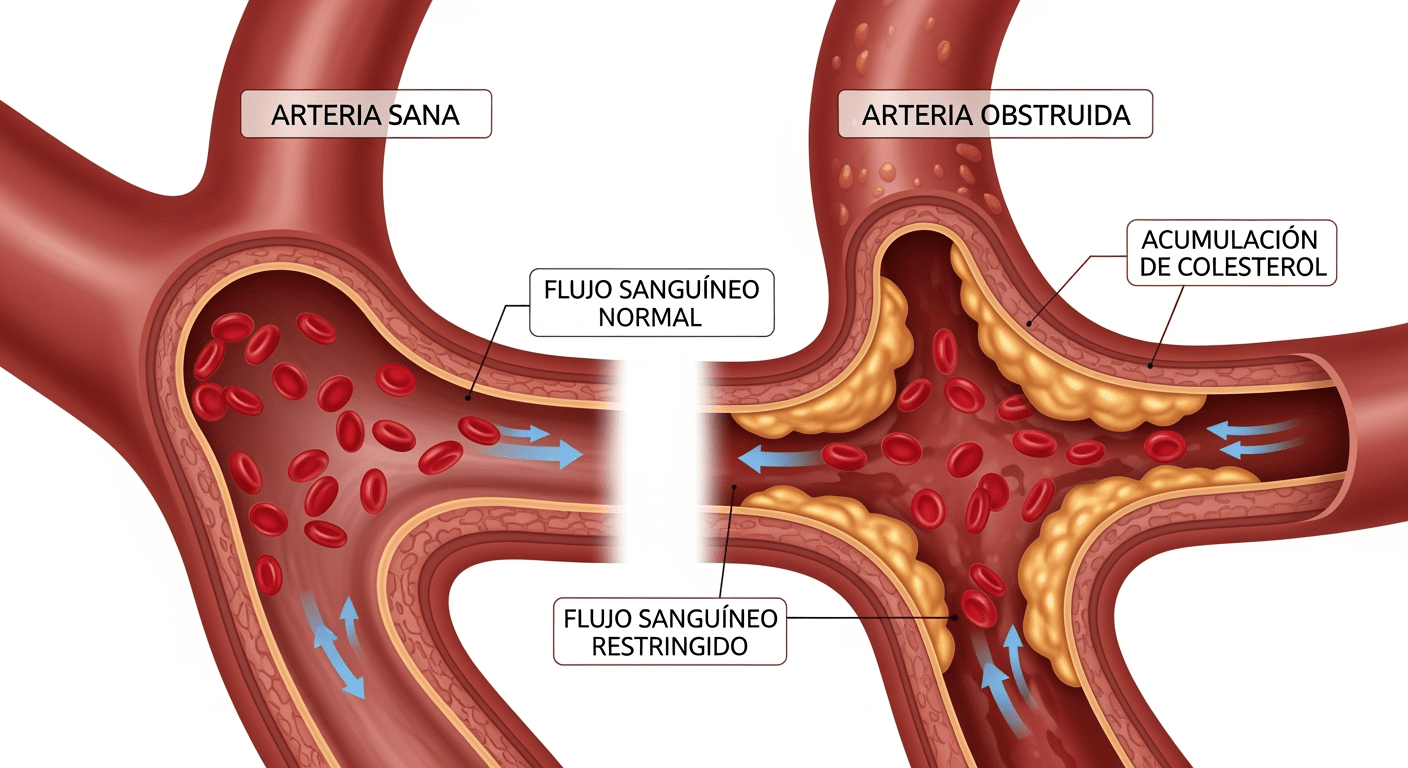

Colesterol bueno y colesterol malo

El colesterol se transporta en la sangre a través de lipoproteínas. Las dos principales son:

LDL (lipoproteína de baja densidad)

Conocido como colesterol «malo», puede acumularse en las paredes de las arterias.

HDL (lipoproteína de alta densidad)

Conocido como colesterol «bueno», ayuda a transportar el exceso de colesterol hacia el hígado para su eliminación.

Cuando los niveles de LDL son demasiado altos, se pueden formar placas en las arterias, reduciendo el flujo sanguíneo y aumentando el riesgo de enfermedades cardiovasculares.